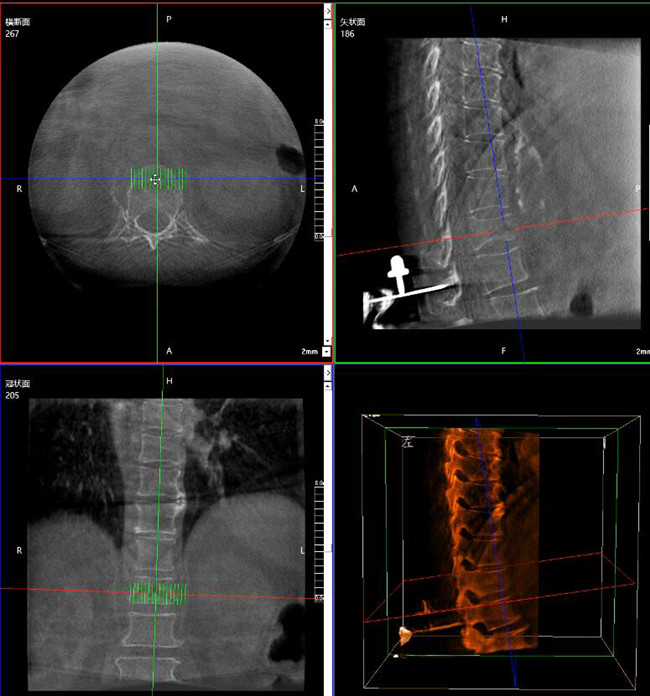

步驟一:C形臂三維重建+機器人手術(shù)規(guī)劃

使用普愛醫(yī)療三維C形臂對患者進行胸椎影像掃描及三維重建,圖像被同步傳輸?shù)狡諓坩t(yī)療骨科機器人導(dǎo)航系統(tǒng)。

C形臂三維重建+骨科機器人手術(shù)規(guī)劃

借助骨科機器人的規(guī)劃軟件進行術(shù)前手術(shù)路徑模擬規(guī)劃,找到穿刺位置和角度,操作機械臂快速完成手術(shù)入點的準確定位。

*術(shù)前規(guī)劃